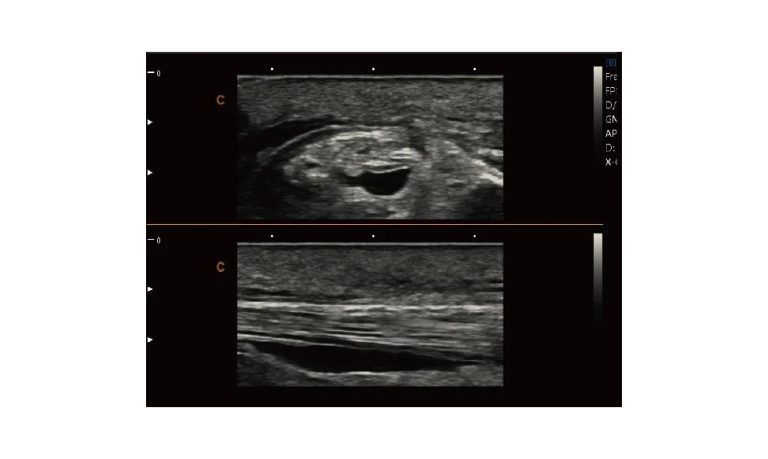

SonoBook

Smart Laptop with Premium Performance

Genius Light Powerful Thin Accurate Fast Quickly

All The Aspects Are Ready To Go